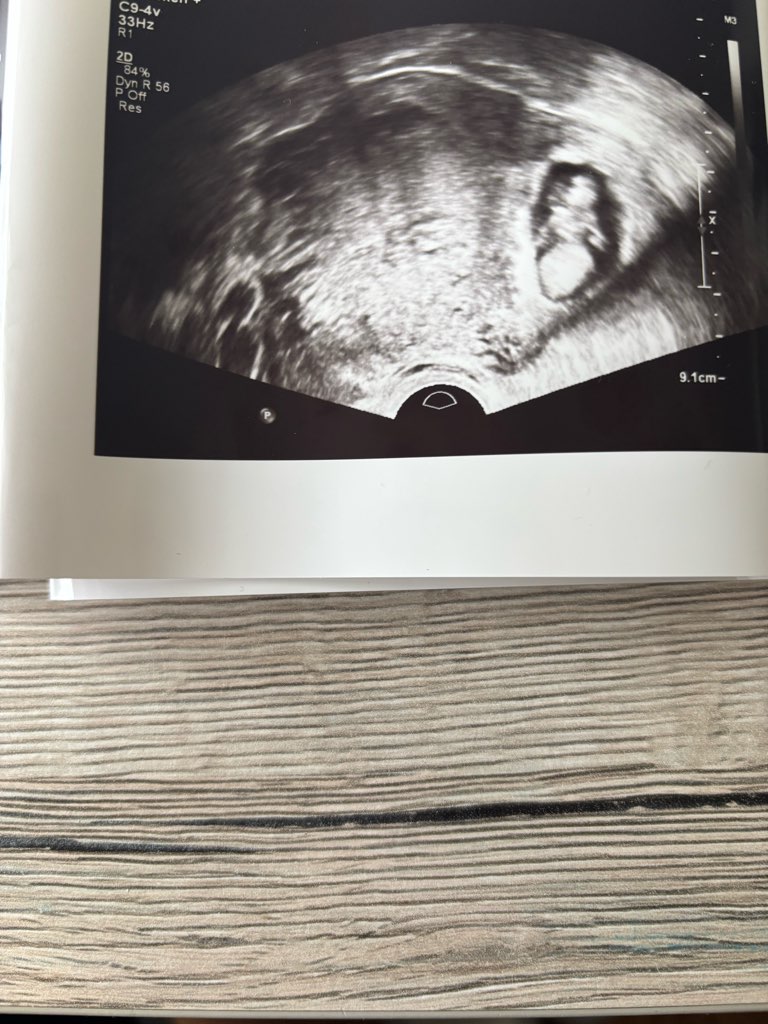

Dziewczyny jestem taka szczęśliwa moje maleństwo ma 3,2cm i jest o jeden dzien większe. Słuchalismyserduszka bije 172 bpm. Termin mi się zmienił ale na razie zostawiam taki jaki był. Ma 2 raczki i 2 nóżki a w brzuchu był taniec 💃🏼 🕺🏼

• IMG_3170.jpeg

IMG_3170.jpeg

2,1 MB · Wyświetleń: 98